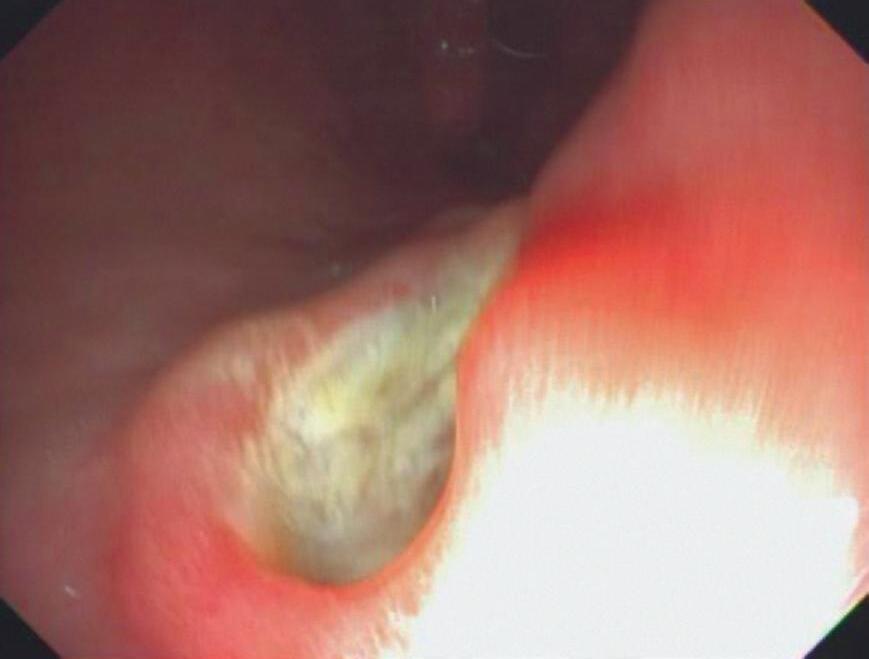

2. Paciente do sexo masculino, 20 anos de idade, previamente hígido, procura atendimento com queixa de disfagia importante de início súbito há 2 dias, referindo dor retroesternal e dificuldade até para engolir saliva. Nega febre, tosse ou sintomas respiratórios. Relata uso recente de um comprimido de anti-inflamatório não esteroide (AINE) para dor muscular, ingerido sem água e imediatamente antes de deitar. Foi submetido à endoscopia digestiva alta (EDA), cujo achado está demonstrado na Figura 4.2. Qual o diagnóstico mais provável e a conduta inicial recomendada?

Figura 4.2 (A e B) Endoscopia digestiva alta mostrando úlceras esofágicas em paredes opostas, chamadas kissing ulcers

Fonte: imagem pertencente à Dra. Caroline Tatim Saad.

2. Resposta C

O quadro clínico típico de esofagite medicamentosa inclui dor retroesternal e disfagia após ingestão de certos medicamentos sem água e/ou em posição supina. A endoscopia revela úlceras lineares em paredes opostas, chamadas kissing ulcers no esôfago médio, geralmente onde o comprimido permanece impactado. A conduta inclui suspensão do fármaco, uso de inibidores da bomba de prótons (IBP) e orientação para ingestão dos comprimidos com pelo menos 200mL de água, em posição ereta e evitando deitar-se logo após. Ao se prescrever qualquer medicamento, muitas vezes não é lembrado de dar as orientações sobre como o paciente deve ingerir, da importância da posição corporal, jejum ou não, ingestão de líquidos, higiene da boca (como no caso dos corticoides inalatórios para asma), por ser situação habitual para os médicos. Porém, essa informação não é de conhecimento de grande parte da população e pode prevenir uma série de complicações relacionadas à forma de administração de medicamentos.